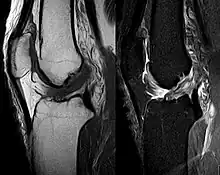

Procédés d'imagerie

Le diagnostic peut être confirmé par imagerie (IRM). Mais il faut noter que l'interprétation de l'IRM seule pour le diagnostic de rupture de LC conduit à 20 % de faux diagnostics. Cela dépend des images de coupe et de la position appropriée du genou pendant l'IRM. Le radiologue doit connaître avec précision les circonstances qui ont conduit à la blessure, et avoir aussi une bonne expérience de l'étude d'une articulation blessée, pour éviter les faux diagnostics. Pour comparer avec l'IRM, le taux d'erreur du test de Lachman, bien plus simple à accomplir, n'est que de 10 %[104],[105],[106],[107]. L'IRM est donc généralement moins sensible et moins spécifique que l'examen clinique par un orthopédiste qualifié[108]. Le résultat de l'IRM n'a que relativement rarement une influence sur la formulation finale du diagnostic[109] et ne devrait pas servir de remplacement pour une anamnèse soigneuse et la palpation[15]. Plusieurs études arrivent à la conclusion que l'IRM n'a de sens que pour des blessures complexes difficiles à expliquer, et là, pour éviter de poser un diagnostic négatif[110],[111],[112].